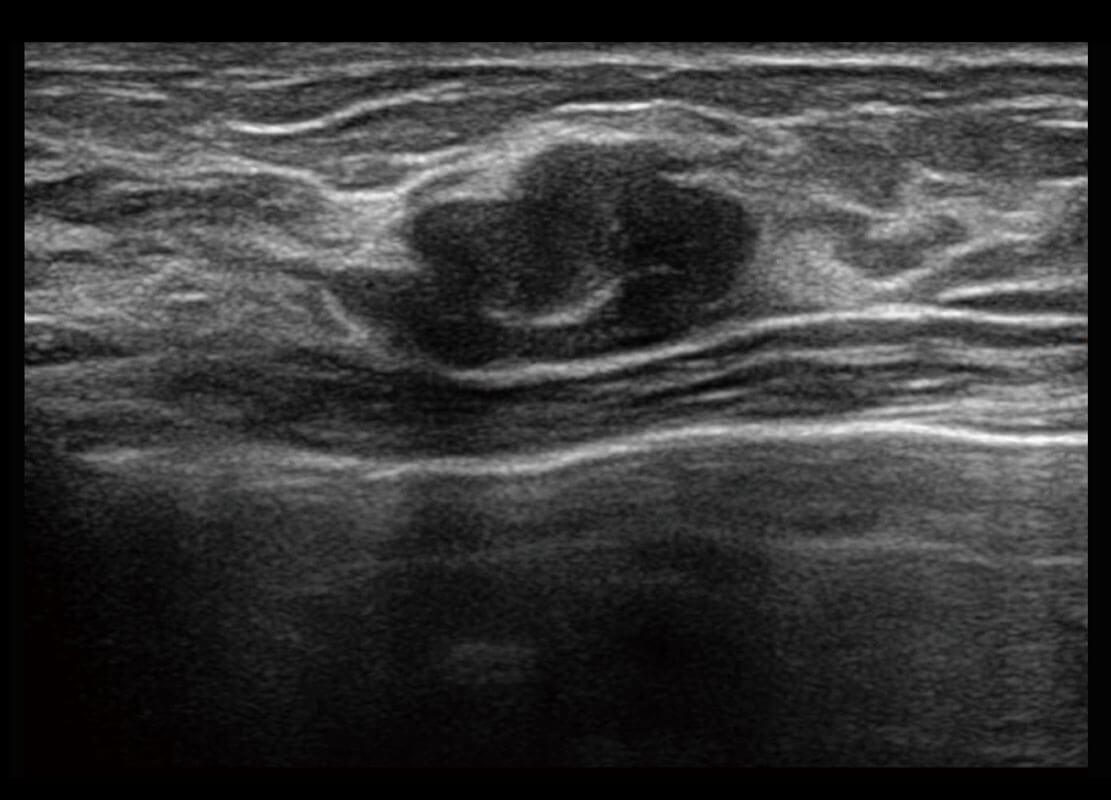

P60搭載寬頻帶線陣探頭、寬景成像、彈性成像技術(shù),為您提供乳腺應(yīng)用方案。P60支持高頻相控陣探頭、線陣探頭、腹部高頻探頭、腹部微凸探頭等,豐富的探頭群搭載敏感的彩色血流成像,適用于新生兒多種臟器檢測要求,滿足新生兒篩查需求。

乳腺導(dǎo)管癌

乳腺癌顯微血流